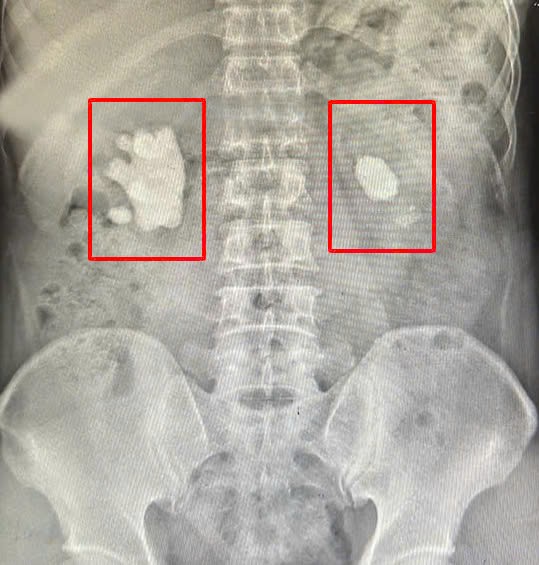

Sỏi thận 2 bên của người bệnh (vùng khoanh tròn màu đỏ).

Sau khi nhập viện, người bệnh được thăm khám và chụp Xquang, cắt lớp vi tính. Kết quả chụp cho thấy, ông Đ. có sỏi thận 2 bên, khối sỏi lớn hình dạng giống san hô chiếm gần hết bể thận.